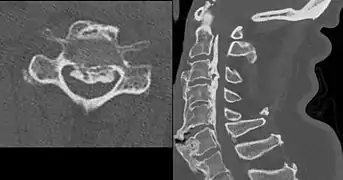

DISH in an 80 year old female, also with T11 fracture.

DISH can be a complicating factor when suffering from trauma involving the spine. It increases the risk of unstable fractures involving the intervertebral disc and the calcified/ossified ligaments which influences the need for surgical treatment.[8]

DISH is diagnosed by findings on x-ray studies. Radiographs of the spine will show abnormal bone formation (ossification) along the anterior spinal ligament. The disc spaces, facet and sacroiliac joints remain unaffected. Diagnosis requires confluent ossification of at least four contiguous vertebral bodies.[2] Classically, advanced disease may have "melted candle wax" appearance along the spine on radiographic studies.[13] In some cases, DISH may be manifested as ossification, or enthesis, in other parts of the skeleton.